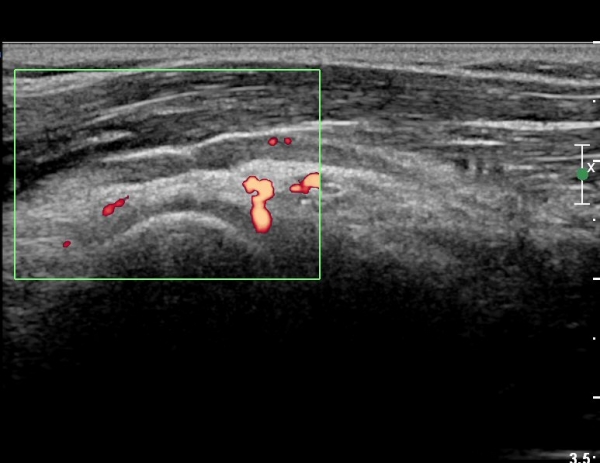

µµÇ÷¯°Ë»ç¿¡¼ ÇùÂø ºÎÀ§¿¡ Ç÷·ùÁõ°¡¸¦ º¸ÀÌÁö ¾Ê¾Æ Ç÷°ü(leash of Henry)¿¡ ÀÇÇÑ ÇùÂøÀº ¹èÁ¦µÈ´Ù(»çÁø 5)